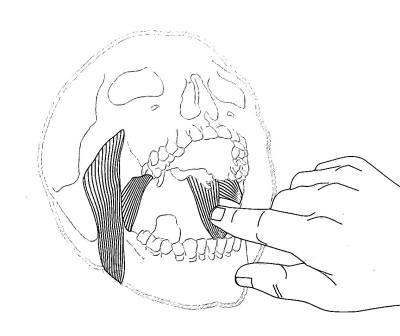

Palpación del haz inferior del pterigoideo externo: |

Para palpar el haz inferior del pterigoideo

externo, se realiza con el dedo meñique y se lo ubica por

delante del pilar anterior hasta la zona de tuberosidad. En

ese momento se desliza el dedo hacia atrás, con presión

moderada. El paciente puede sentir una molestia moderada,

hasta un dolor exquisito.

Si existe dolor intenso a la

palpación es señal de que el paciente presenta bruxismo. |